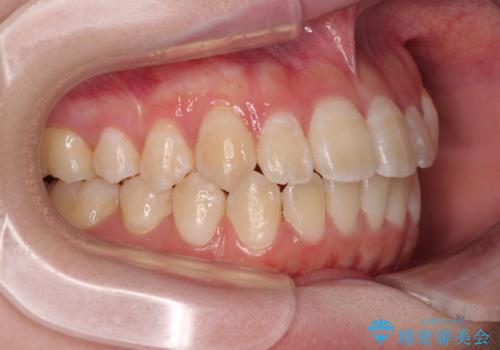

上下の正中(真ん中のライン)もずれることなく、バランスの取れた美しい歯並びに。笑顔に自信を持てる仕上がりとなりました。

「もっと時間がかかると思っていましたが、あっという間でした。装置も思ったより気にならず、前歯がきれいに並んでとても満足しています。」とうれしいお言葉をいただきました。